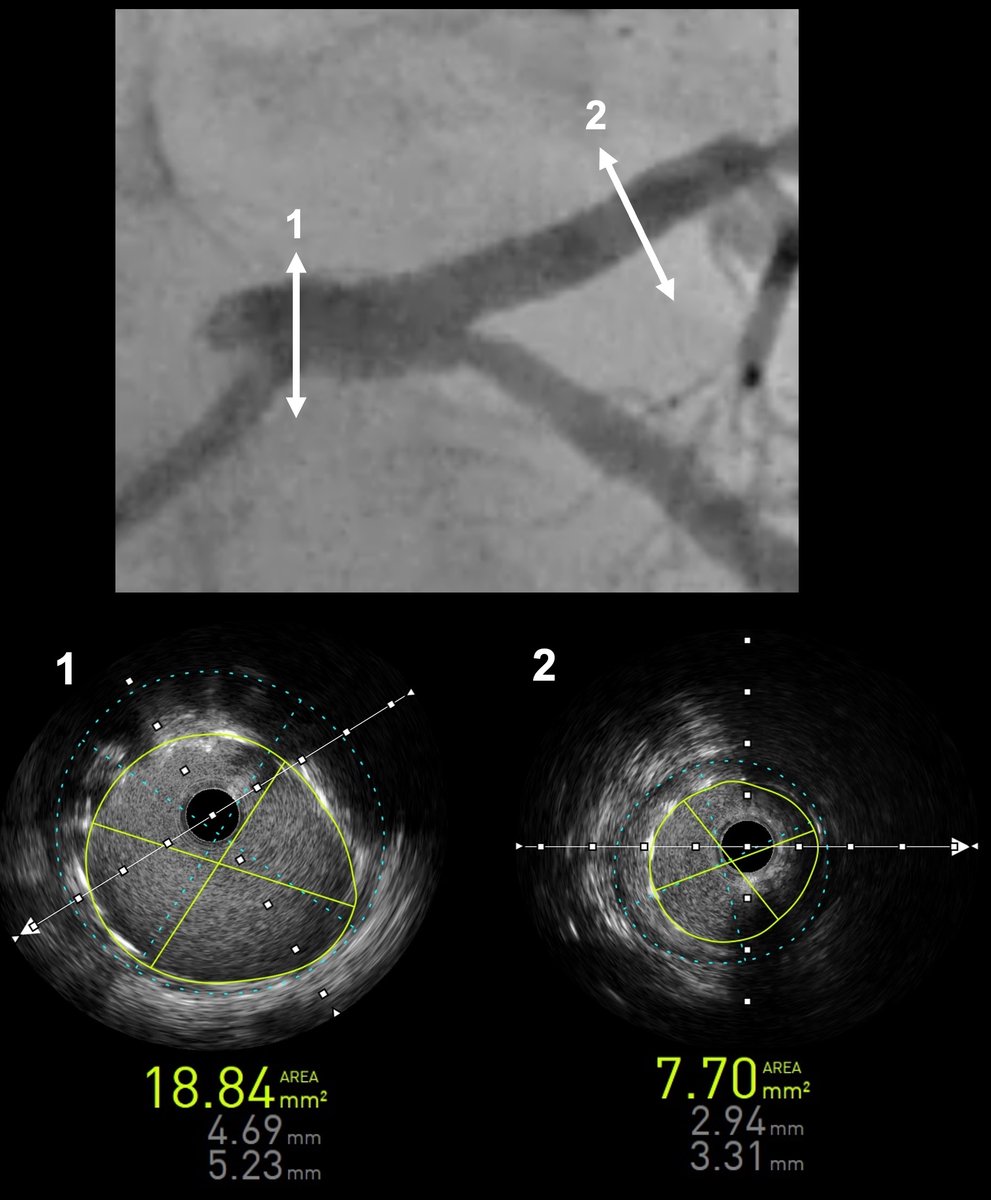

A 78-year-old man with stable angina and a calcified LAD lesion underwent PCI planned using a multimodal calcium assessment. X-ray–based Ca²⁺ mapping with 3DStent, correlated with CT and IVUS, provided 3D visualization of calcium burden and informed plaque preparation.

Analysis of distal and proximal stent areas showed good correlations between #3DStent from @GEHealthCare and #IVUS images and measurement. Images & case performed at @ICPS_institut

New #3DStent stent enhancement technology opens new perspectives for LM PCI assessment by providing accurate analysis of device deployment, expansion and structure. In this case, post PCI analysis revealed absence of longitudinal compression and adequate POT results.